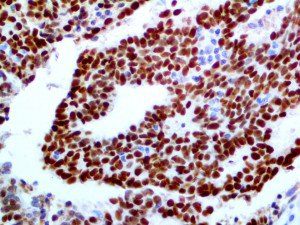

It is the ICU physician who is most likely to witness one of the deadliest manifestations of the abnormal immunological response, the cytokine storm syndrome (CSS). This response is also referred to by some as the cytokine release syndrome (CRS). CSS is characterized by continuous activation and expansion of macrophage and lymphocyte populations, which secrete large amounts of cytokines, causing the cytokine storm. This massive cytokine release is akin to hemophagocytic lymphohistiocytosis (HLH) disease, a syndrome characterized by initial unchecked and persistent activation of cytotoxic T lymphocytes and NK cells.

Clinical and laboratory manifestations of HLH include fever, enlarged liver and/or spleen, neurologic dysfunction, coagulopathy, liver dysfunction, cytopenias (i.e., low levels of erythrocytes, leukocytes, and/or platelets), hypertriglyceridemia, hyperferritinemia, hemophagocytosis, and eventually diminished NK cell activity as the immune system becomes progressively paralyzed. HLH can be familial (primary HLH) or secondary to another disease process (sHLH), such as rheumatic disease, in which it is referred to as macrophage activation syndrome (MAS, characterized by elevated ferritin).

This activation induces inflammatory monocytes to highly express IL-6, starting a localized and then systemic cascade effect that results in hyperproduction of IL-6, which accelerates the inflammatory process. Because IL-6 also increases vascular permeability, excessive levels cause blood vessels to become very leaky. This, along with clotting factors released from vascular endothelial cells, stimulates the coagulation cascade, resulting in microthrombosis (tiny clots), which leads to ischemia and tissue death of the kidney, intestines, heart, liver, brain and extremities.